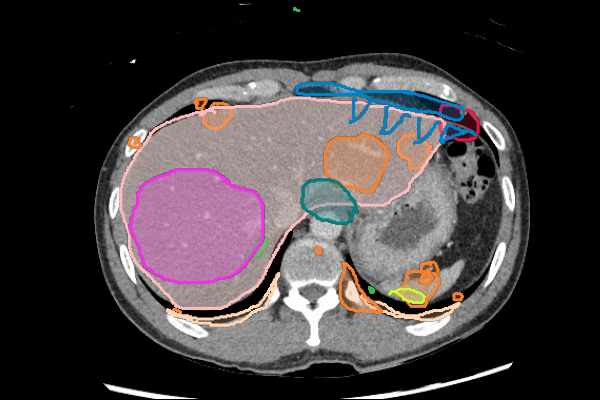

Legend

Slice 1